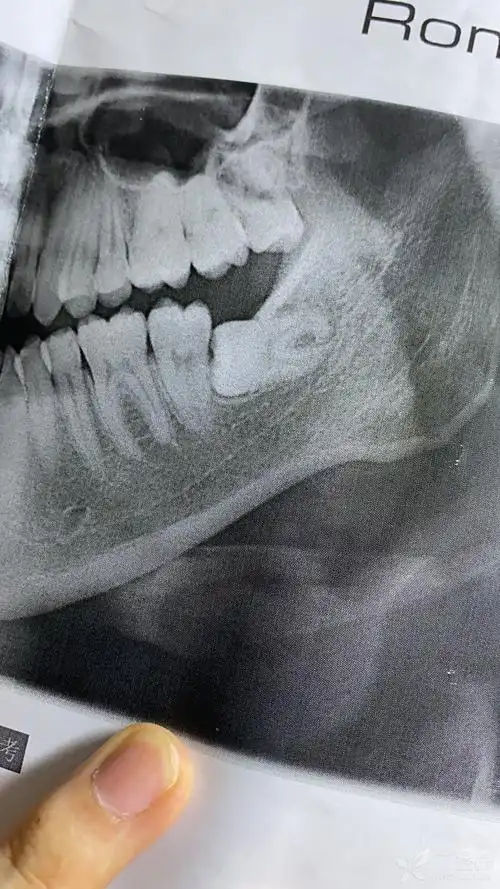

口腔专业的学长学姐们,请问我左边这颗智齿拔的话风险很大吗